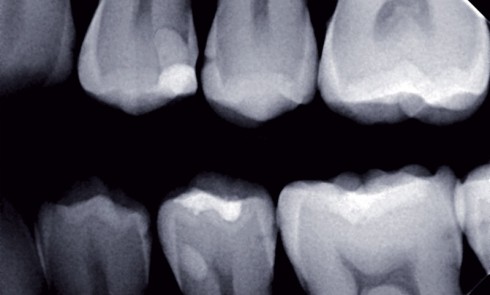

L’approche médicale des lésions carieuses dentaires requiert une détection de ces lésions à un stade le plus précoce possible. La...

L’imagerie conventionnelle (2D) Argentique ou numérique, ses deux versions ne diffèrent que par la nature du capteur (film ou récepteur...